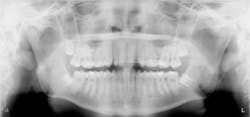

The following case study shows a Caucasian male, age 15 at the beginning of treatment. He had a peg lateral incisor No. 7 and was congenitally missing tooth No. 10. The treatment plan consisted of positioning tooth No. 7 for a veneer and opening space for an implant to replace tooth No. 10. After 30 months of orthodontic treatment had elapsed, there was still insufficient room for implant placement. There was sufficient room for the crown of No. 10, but the roots of teeth Nos. 9 and 11 were still too convergent to allow implant placement. The patient was leaving for college soon and was anxious to have treatment completed. The decision was made to have a periodontist do a corticotomy surgery to accelerate the tooth movement.

Corticotomy surgery was done and distal root movement was initiated on tooth No. 11 using a lever arm and elastic power chain. Root divergence was accomplished in eight weeks, and implant placement was accomplished at that time. The occlusion was detailed and orthodontic appliances were removed a short time later.